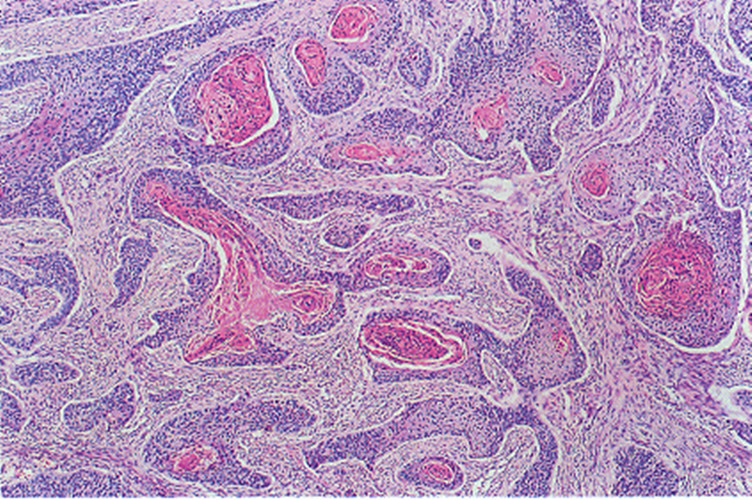

顯微鏡下惡性喉腫瘤